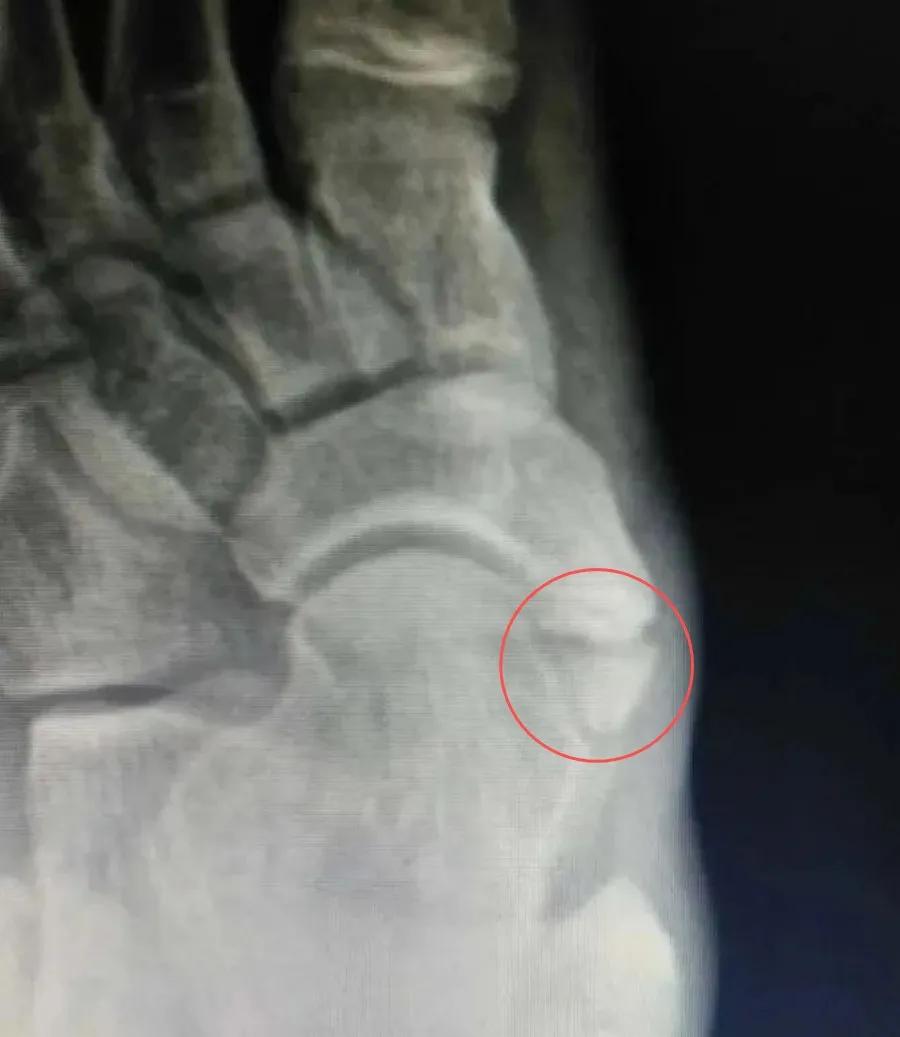

足的副舟骨是舟骨结节部第二化骨中心的先天异常,在舟骨结节处形成一个独立的副骨,多为双侧。表现为足内侧隆起,久站或行走较长时, 足底内侧感到疼痛(箭头处)。

通过1-2毫米厚的纤维软骨或透明软骨与舟骨相连,形成微动关节;X 线片上在舟骨与副舟骨之间形成透亮线,有时被误认为舟骨骨折。占副舟骨的约55%。最常见疼痛。

X线:足舟骨结节内后方有边缘整齐的小骨块,密度同舟骨(下图)。